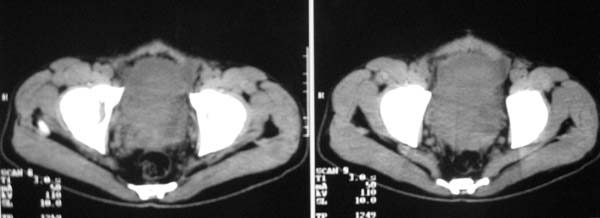

以下是引用zjzjr在2007-9-27 22:20:00的发言:[br]肠腔受推移,未见明显扩张及液平,所以考虑是肠外病灶, 间叶源性肿瘤?脂肪瘤?建议增强。

以下是引用guzhongliangddd在2007-9-27 23:21:00的发言:[br][br]与肠内高密度相同,病灶应该没有钙化,我认为首先考虑是间叶组织的良性肿瘤。建议楼主做后重建观察。中线区域大血管旁未见确切增大淋巴结。病灶对肠道只是推移关系。

以下是引用余辉在2007-9-27 22:24:00的发言:[br]暂考虑肠道间质来源肿瘤如小肠平滑肌肉瘤/瘤可能,应该增强